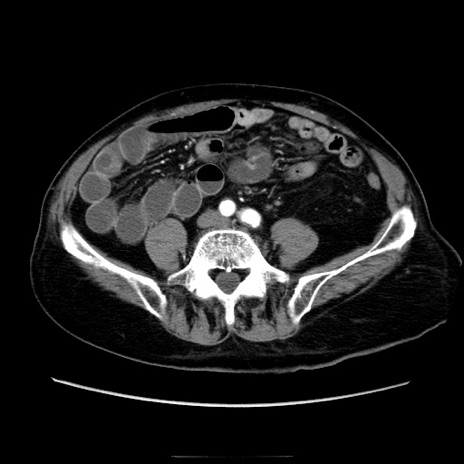

症例21(横断像)

【症例】70歳代男性

【主訴】腹痛

【現病歴】肝硬変・肝細胞癌にてかかりつけの方。約9時間前に食後より腹痛出現。症状が徐々に増悪し、嘔吐出現したため来院。

【既往歴】肝硬変、肝細胞癌(RFA、TACE後)

【身体所見】意識清明、表情苦悶様、BT 36℃、BP 129/78mmHg、P 88bpm、SpO2 97%(RA)、右上腹部から心窩部にかけて圧痛あり、反跳痛なし、筋性防御あり。

【データ】WBC 5800、CRP 0.16